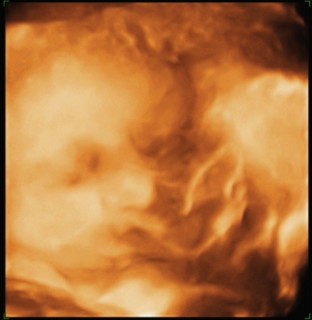

ほっぺたがぷっくり出てて、目鼻立ちは夫そっくり!髪の毛も生え始めてました。

このときの推定体重は約2.2キロでしたw

3Dエコーでとってもらいました。

天使みたいな寝顔!(はい。すでに親バカです)